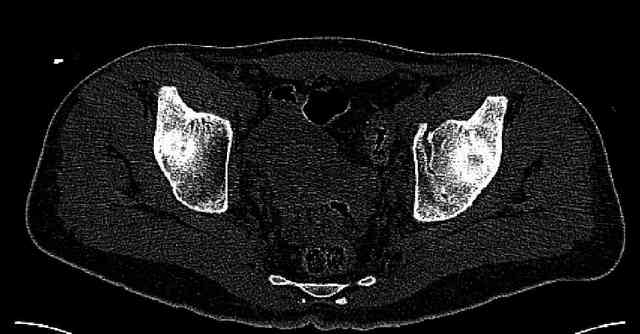

Some more images. Does it help to guess which part of the acetabulum is displaced?